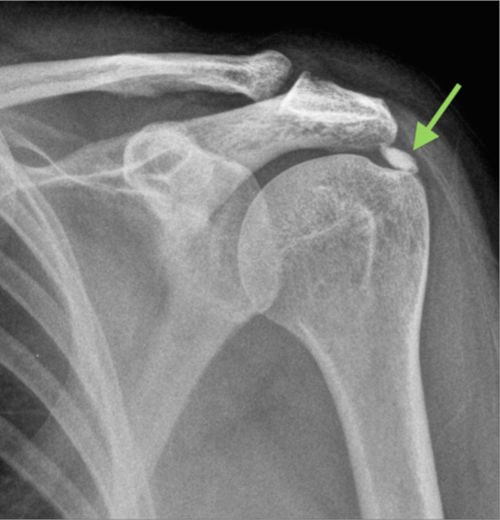

Ακτινολογική ταξινόμηση της ασβεστοποίησης στον ώμο (Gartner and Hayer)

Ανάλογα με την απεικόνιση στην ακτινογραφία ταξινομείτε ως εξής:

| Τύπος Ι : Ομαλά όρια, αυξημένη πυκνότητα ασβέστωσης. Φάση σχηματισμού | Τύπος ΙΙ: Σχήμα ομαλό, πυκνό ή οξύ, περιοχές ακτινοδιαπερατές. Φάση σταθεροποποίησης | Τύπος ΙΙΙ: Διάφανη, νεφελώδης εμφάνιση, χωρίς σαφή όρια. Φάση απορρόφησης |